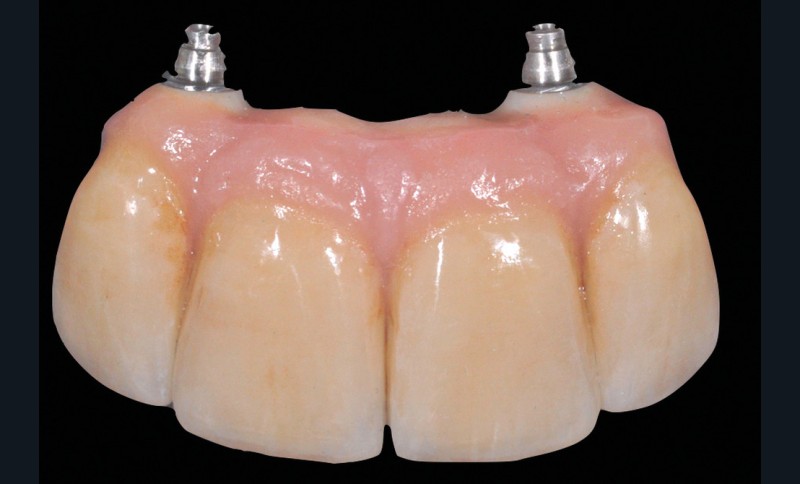

Au moment du scellement, la suprastructure est remplie du matériau d’assemblage, puis positionnée entièrement, mais sans pression, sur ce duplicata, et immédiatement retirée pour être positionnée sur le pilier implantaire en bouche (fig. 4).

Il s’agit cette fois de visser un pilier implantaire sur l’implant, sur lequel se fixe une coiffe prothétique transvissée. Il y a donc plusieurs étages dévissables et un trou d’accès à la vis (puits) dans la face occlusale de la couronne.

Les études montrent que si le puits est proche du centre, en ménageant 2 mm au moins de céramique autour, le risque de fracture est faible. D’où l’intérêt d’un excellent positionnement implantaire (fig. 6).

Mais depuis plusieurs années, la prothèse évolue pour les secteurs postérieurs vers des restaurations monoblocs usinées en céramique, collées ensuite au laboratoire à une embase en titane. Cet élément massif d’un seul matériau aux propriétés mécaniques élevées (disilicate de lithium ou zircone) est en train de faire quasiment disparaître les fractures de céramique.